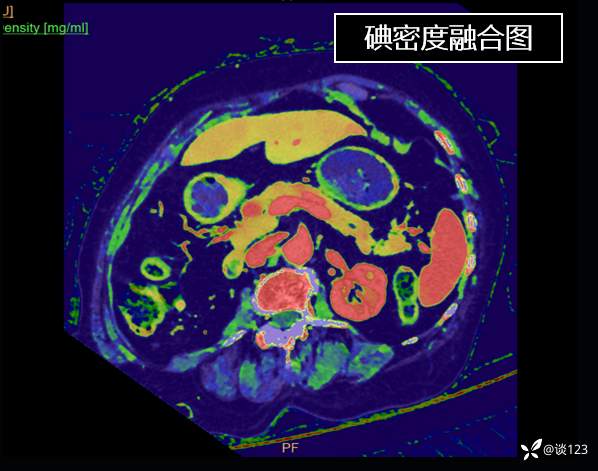

重新针对CT进行多参数后处理

这类病变不结合病史的情况,即使在CT静脉期有所异常也容易忽略;同时针对该类疾病使用胰腺增强方案应该更佳,好的诊断先决条件还是技术,技术不够CT新技术来凑。